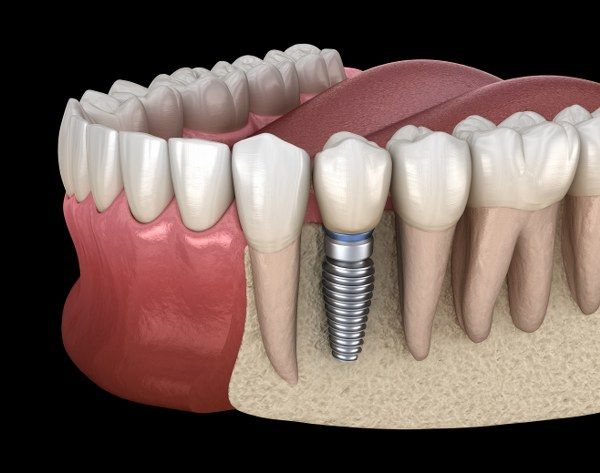

O implante é um “parafuso” de titânio colocado dentro do osso para substituir a raiz do dente perdido. Ele serve como base para fixar uma prótese que parece e funciona como um dente natural.

O procedimento é feito com anestesia local e, na maioria dos casos, é indolor. Após a cirurgia pode haver um leve desconforto, controlado com analgésicos comuns.

A maioria dos pacientes retorna às atividades leves no dia seguinte. A cicatrização óssea completa (osso unindo ao implante) costuma levar de 3 a 6 meses, dependendo de cada caso.